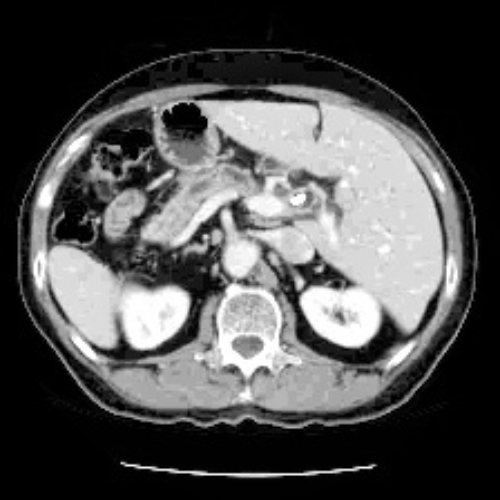

As shown in Fig. 2, we ensure that contrast enhancement is applied dynamically and adapts to each individual image by leveraging the underlying grayscale intensity distribution, rather than imposing uniform adjustments across the entire dataset. The enhanced output is subsequently validated and converted to an 8-bit representation to ensure numerical stability and compatibility with downstream processing. The pipeline supports parallel batch processing with consistent configuration settings, while allowing key parameters, such as the background intensity threshold, percentile bounds for contrast stretching, CLAHE clip limit [48], and tile grid size, to be tuned for specific datasets. Artifact suppression is achieved through smooth histogram redistribution, bilinear interpolation between tiles, and edge-aware processing strategies. This preprocessing design is particularly well suited for low-contrast medical images, especially CT and MRI scans, where preserving subtle anatomical details is essential for reliable diagnosis and accurate segmentation in subsequent deep learning pipelines.

For experimental evaluation, we leveraged three publicly available medical imaging datasets. The FLARE22 dataset [33] served as the primary source for training and validation, while additional samples from the SAROS [40] and CHAOS [25] datasets were incorporated for extended testing and validation. All datasets comprise abdominal CT and MRI scans provided in NIfTI format; however, instead of processing full 3D volumes, we extracted 2D axial slices for analysis. Middle axial slices were selected, as they consistently offer clear visualization of key abdominal organs and representative anatomical context. While FLARE22 forms the core experimental dataset, the inclusion of SAROS and CHAOS enables assessment of the robustness and generalizability of the proposed approach across varying imaging protocols and scanner characteristics.